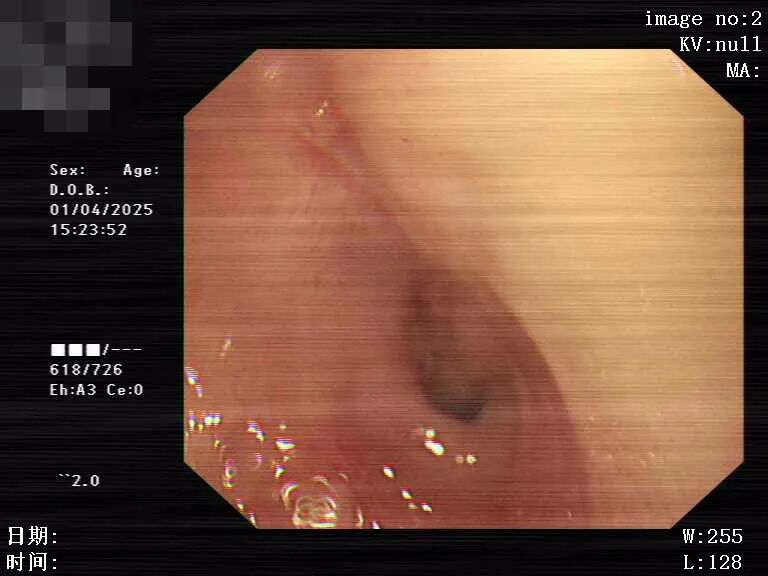

据悉,该患者为男性,因“脑出血后遗症”出现“吞咽困难半年余”入院,此前长期留置胃管(经胃管注食营养支持治疗)。入院2天前患者自行拔除胃管,家属(家属为医务工作者)反复尝试重插胃管失败。患者出现吞咽困难,无法进食,遂到廉江市人民医院门诊就诊。门诊行胃镜检查提示“食管狭窄”,收住消化内科进一步治疗。

图片

食管狭窄

入院后完善相关检查,诊断该患者不仅有吞咽困难、食管狭窄、脑出血后遗症,还有多发腔隙性脑梗死、脑积水、鼻窦炎等十余种基础疾病,且患者高龄,长期卧床,外科手术风险高。此外,患者因食管狭窄导致无法常规留置胃管,且长期留置胃管容易引起食管粘膜损伤出血及狭窄,这使得营养支持成为维持其生命的关键难题。